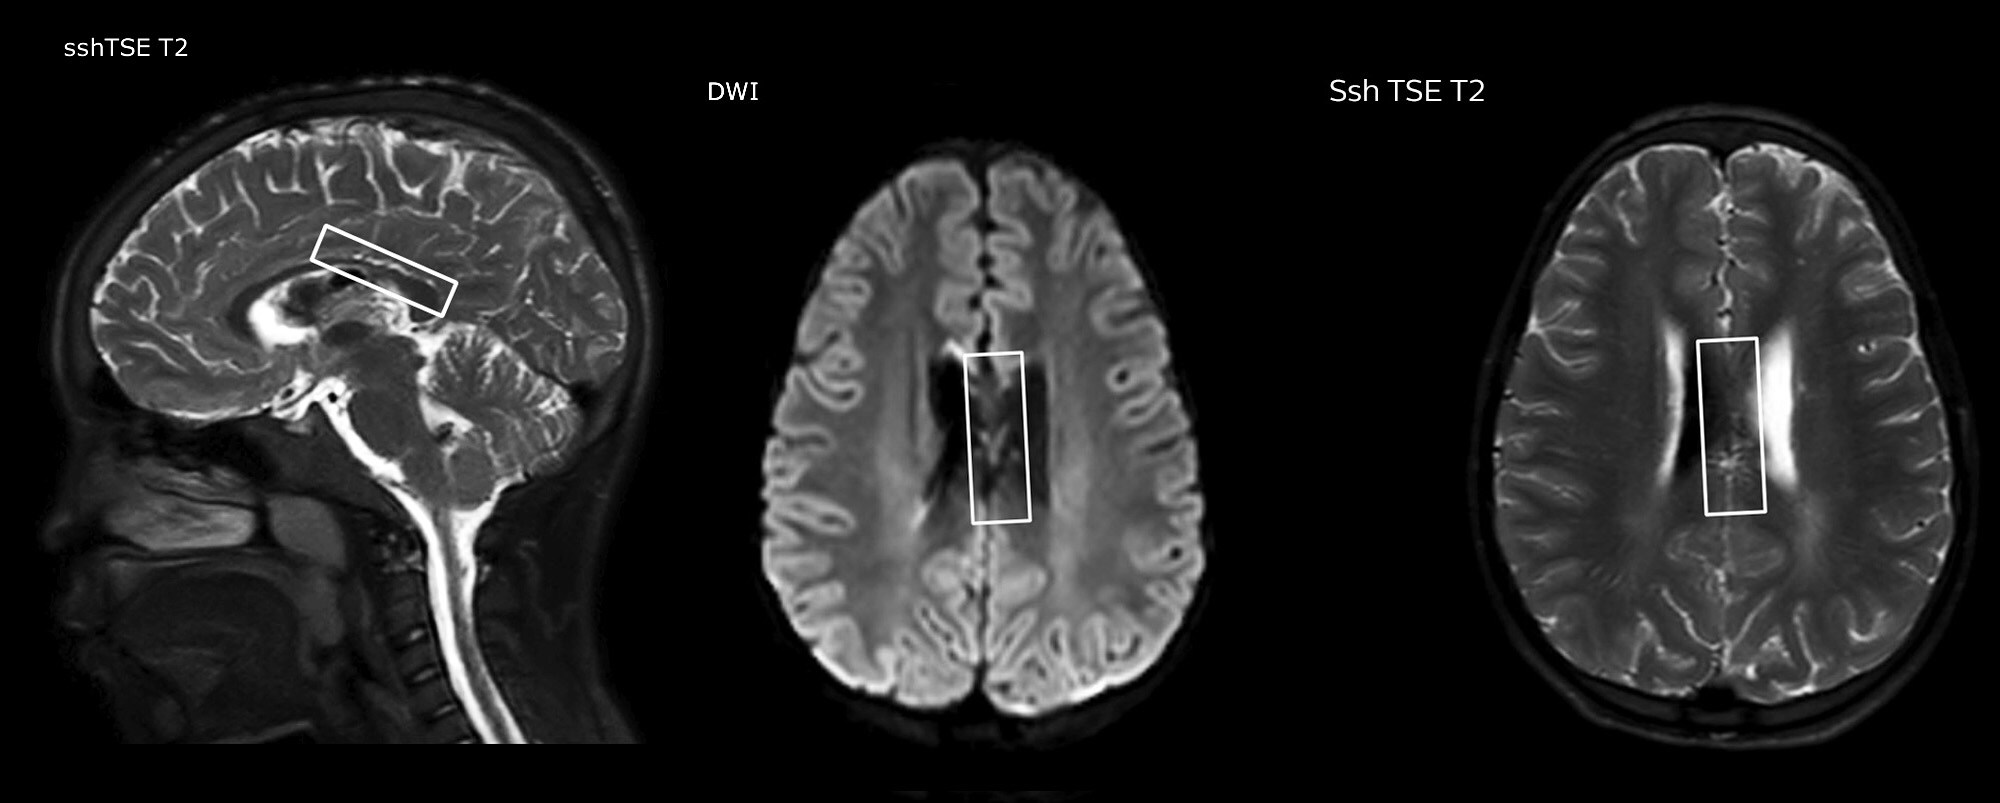

2. Magnetic resonance imaging

Magnetic resonance imaging

MRI clinical applications

Clinical cases from nearly every anatomy

Explore 200+ clinical cases and download exam cards from peers around the globe, showcasing how Philips MR technology enhances your imaging capabilities.